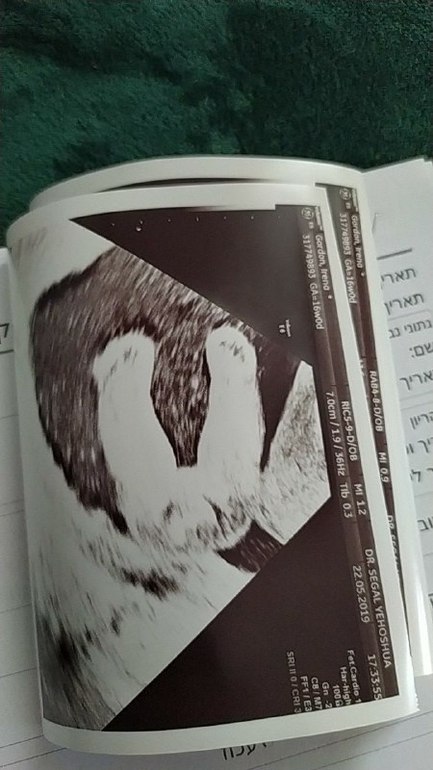

Сегодня ровно 16 недель. Первый скрининг.

Девочка.

Проверка показала что всё в норме. Всё посчитано, руки, ноги и даже язык....

На УЗИ стопы, вид снизу?))

Стопы на узи вторично))))) Это попа и доказательство что между стоп..ничего)))))) не пацан! Имя тоже уже выбралось))) приче не мной, но мне понравилось. Пока со скрининга до дома доехали, она из безымянного плода ,превратилась во вполне себе девочку с именем)))))